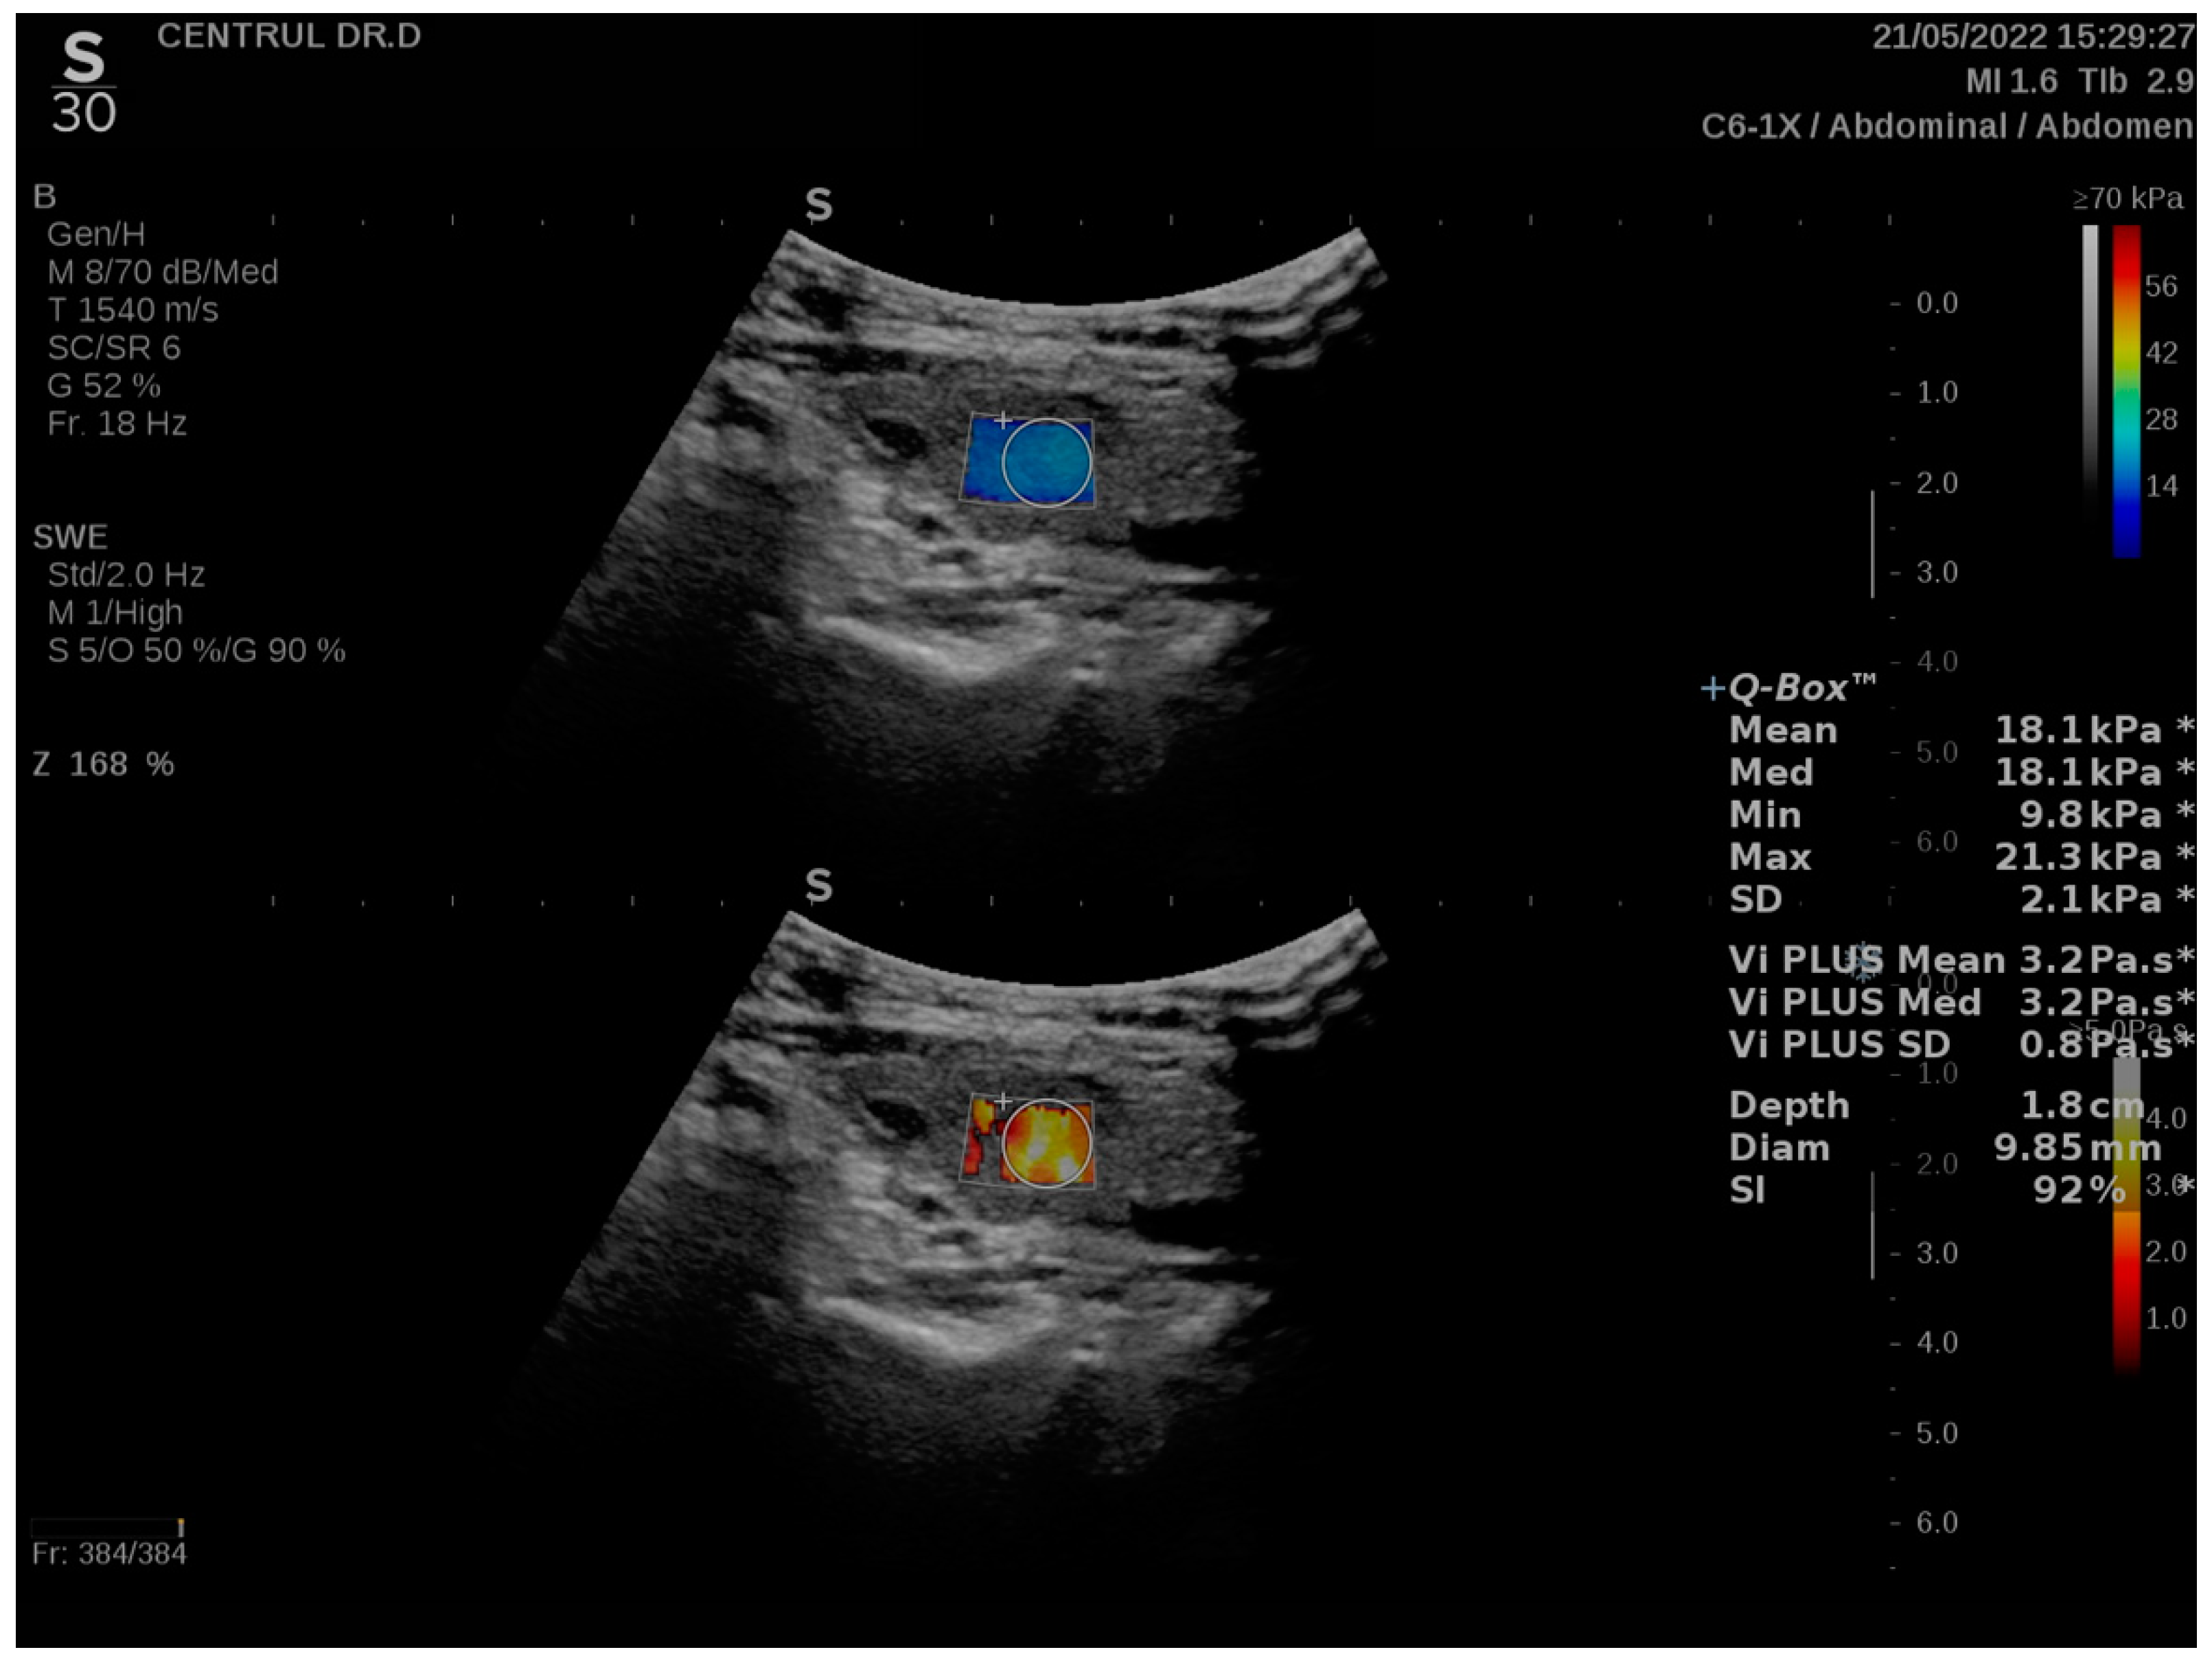

2.2. Ultrasound, 2D Shear-Wave and Vi PLUS Evaluation